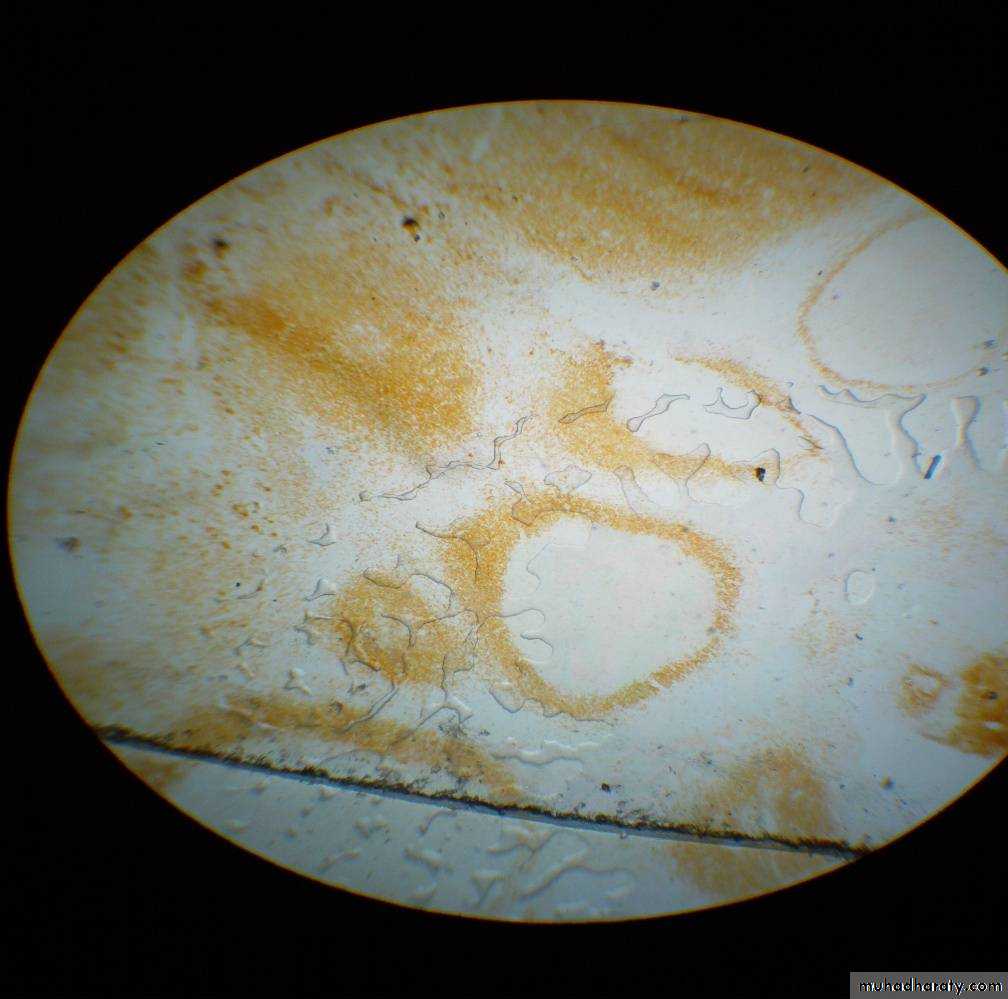

B cell markers : IgM

1ry follicles : Many cells are positive

2ry follicles:M.Z: Many cells are positive

G.C: Meshwork staining

- IFA : few cells are positive

B cell markers: IgD1ry follicles : Many cells are positive

G.C: Few cells are positive

Ring-like appearance